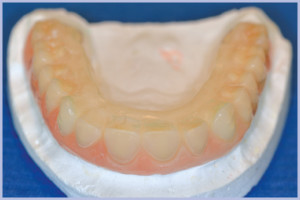

- Fig. 1 – Situazione iniziale

- Fig. 9 – Protesi nuova in composito